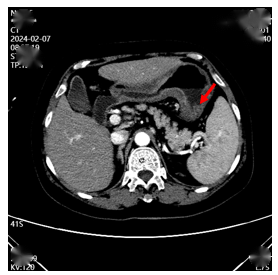

2023年8月16日行CT检查,提示:全腹CT提示胃壁广泛增厚,最厚处约27mm,考虑为胃恶性肿瘤,并伴有胃周、小网膜囊、肝门区、腹膜后等多处淋巴结转移及大网膜转移可能(图1)。胸部及头颅MR未见转移。

图1. 腹部CT检查(2023年8月16日)

2024年2月再次复查CT提示胃壁病灶局部进展,部分淋巴结增大或出现新增(图3),疗效评价为:疾病进展(PD)。

图3.腹部CT检查(2024年2月)